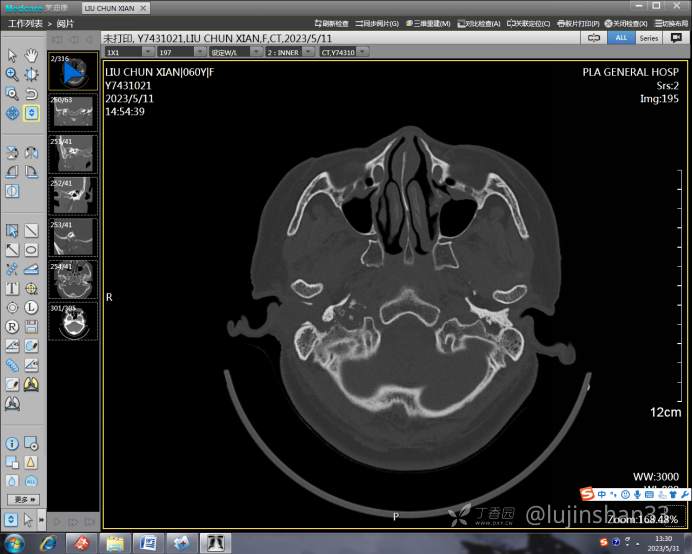

(2023-05-12 10:15,本院)行CT(颅脑)检查提示:右侧颞骨广泛骨质破坏,伴巨大软组织肿块,性质待定,考虑肿瘤性病变,颈静脉球瘤?软骨源性肿瘤?请结合临床及病理进一步明确。